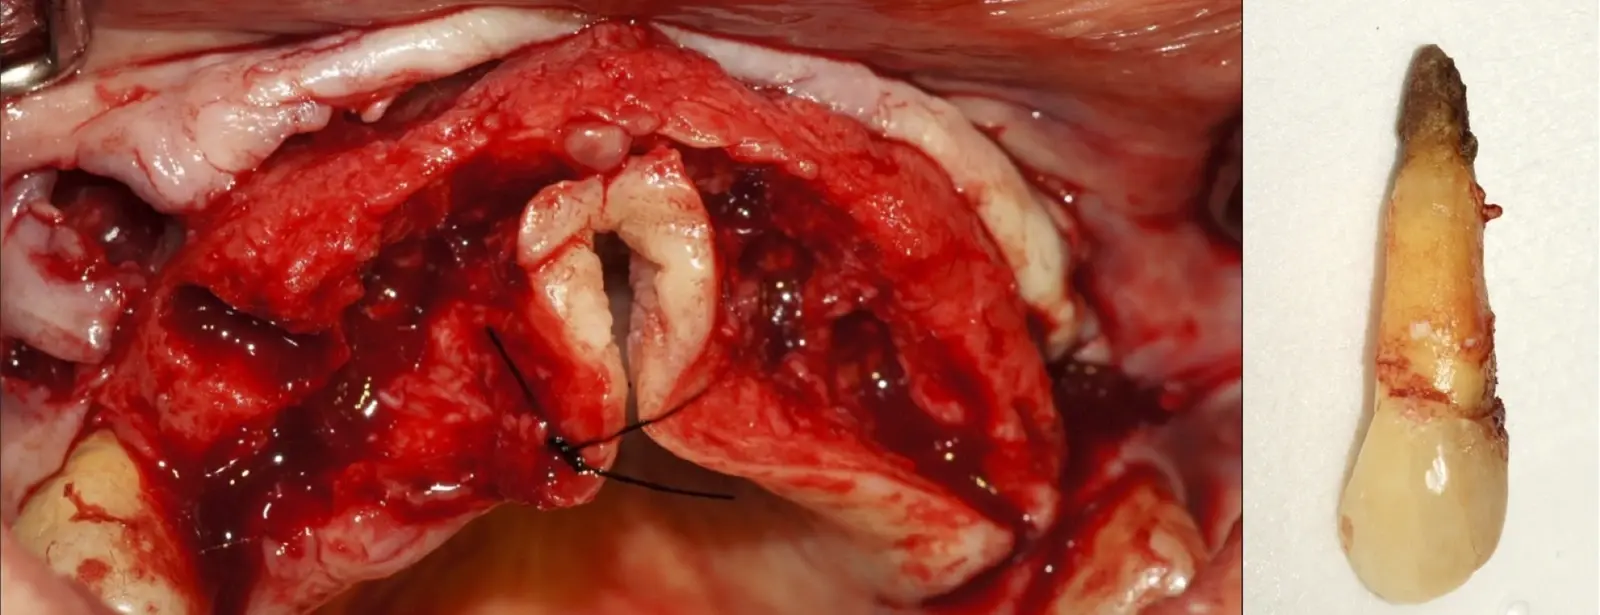

Figura 1. Tomografía cone beam en la que se observa la pieza 1.4 aparentemente normal, sin signos de patologías.

Figura 2. Exodoncia de la pieza 1.4 indicada como parte de una planificación de implantes dentales.

Figura 3. Concrescencia a nivel apical en la pieza extraída.

Figura 4. El mayor aumento de la concrescencia es observa a nivel apical.